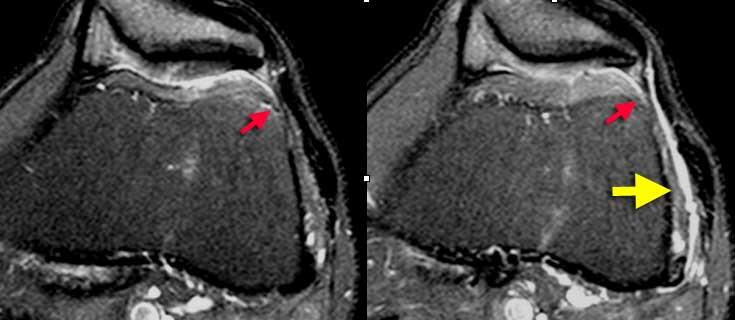

TRÁI: Các bó sợi ACL có hướng bình thường nhưng không bám vào lồi cầu đùi. PHẢI: Dấu hiệu hõm rỗng: dịch áp sát mặt trong lồi cầu ngoài.

Đôi khi dễ đánh giá hơn liệu các bó sợi có còn bám vào xương hay không khi quan sát trên mặt phẳng vành.

Tuyệt đối không được có dịch áp sát mặt trong lồi cầu ngoài.

Nếu có dịch ở vị trí này, được gọi là ‘dấu hiệu hõm rỗng’, cho thấy ACL đã bị bong khỏi điểm bám trên lồi cầu đùi.

Trên mặt phẳng ngang có dấu hiệu hõm rỗng (mũi tên vàng) ở vị trí lẽ ra ACL phải bám vào lồi cầu. Ở mức thấp hơn (sang phải), ACL đứt đã dính sẹo vào PCL (mũi tên xanh lá).

Trên mặt phẳng ngang cũng phải thấy dây chằng nằm sát bên lồi cầu.

Ở mức thấp hơn, chúng ta thấy ACL đứt bám dính vào dây chằng chéo sau.

Chúng đã dính vào nhau thành sẹo.

Đây là hình ảnh rất thường gặp trong đứt ACL mạn tính.

Sự dính sẹo này tạo ra góc gấp cấp tính của dây chằng.

Mặc dù ACL đã dính vào PCL, nhưng vẫn không đủ vững và cần phải tái tạo.